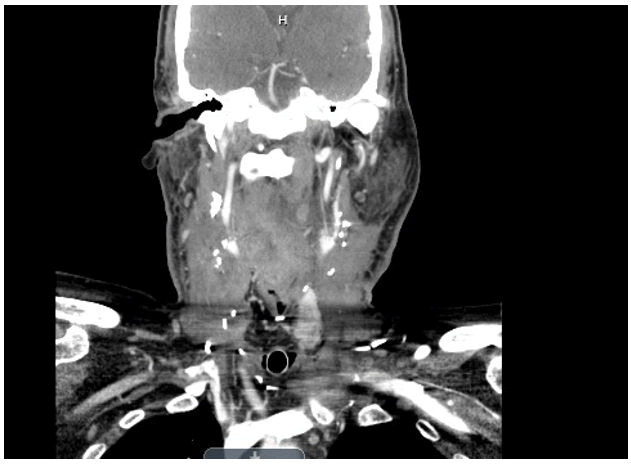

The patient’s platelets remained elevated in the mid-400s (k/mcl). MRA revealed thrombosis of the left and right internal jugular veins. The right IJV was suffering from almost complete occlusion. The thrombosis of the left internal jugular vein was diffuse and involved the jugular bulb, transverse sinus and up to the sigmoid sinus. Neurosurgery was consulted and intervention was not advised. Anticoagulation with enoxaparin was initiated. Hydromorphone was effective for pain control but only for an hour to two. Buprenorphine was eventually initiated and replaced oxycodone. The patient was discharged on apixaban and buprenorphine notably but returned to the hospital about a week later due to inability to tolerate pain. The patient reported only oxycodone and hydromorphone control the pain. It should be noted that the patient was considerably malnourished on admission. The patient’s ability to speak was limited at this point, only some words could be communicated.

Pain management sought to try valproate and dexamethasone for head pain in addition to hydromorphone. The consideration of thrombectomy for the venous thrombosis became a discussion if there was no improvement on duplex ultrasound, which showed limited if any changes. However, neurovascular still advised against intervention. The patient had begun to suffer sinus pauses as well, cardiology considered pacing support but in any case he was kept on telemetry. It was thought to be caused by respiratory distress and intense pain. An ECHO was conducted which fortunately showed normal EF. At this point, the patient was suffering from hyponatremia, folate deficiency, thrombocytosis, leukocytosis, and dysphagia. Additionally, the patient was not able handle salivary secretions, thus requiring intensive medical management. In terms of pain control, the patient was now receiving hydromorphone 0.5 mg q3h and a 75 mcg transdermal fentanyl patch.The patient still suffered from headache but this controlled his pain to a greater degree. Careful attention was paid to tracheal secretions as an episode of desaturation to 88% occurred, thus the patient had suction nearby preferably at all times. The patient suffered an episode of hypercalcemia at 16.4, treated with calcitonin. BMP and other lab values were ordered q12h to stay ahead of any abnormalities. Additionally, an acute kidney injury occurred with Creatinine of 2.6 and BUN of 19. The treatment plan was to give 150 ml/hr of normal saline along with potassium and phosphorus supplementation. The patient suffered increasingly prolonged sinus pauses, one episode over seven seconds. A pacemaker was implanted accordingly. The patient was also suffering from hypotension and midodrine was used in addition to vasopressors when necessary. A PEG tube was attempted but failed due to esophageal stenosis. The patient had an episode of hematemesis, about one liter of blood was lost. The patient was transferred to the ICU for care. ENT recommended packing the throat if bleeding occurred again and ventilating though the laryngostoma The patient was taken to the operating room about a day after the hematemesis episode for PEG tube placement and laryngoscopy. Anti-coagulation was recommended to be held according to ENT, as tumor bleeding was held responsible for the episode of hematemesis. The patient stabilized over the course of about a week and was discharged. The patient returned via EMS after suffering excessive secretions (salivation) and oxygen desaturations upon sitting up. The patient was admitted and treated empirically for an infection. Hemoglobin was 10.1, WBC 22.3 and platelets 561 k/mcl on admission. The bilateral IJV thrombosis still had not resolved at this point. Excessive secretions and blood were seen throughout the laryngostoma. It appeared the patient had either tracheitis or a pseudomonas infection. The patient also had excessive neck swelling, CT showed a necrotic mass on the left side of the neck. At this point, the patient was transferred to a cancer facility for further care (Figure 1).

Figure 1: MRA revealed bilateral thrombosis of the internal jugular veins plural.